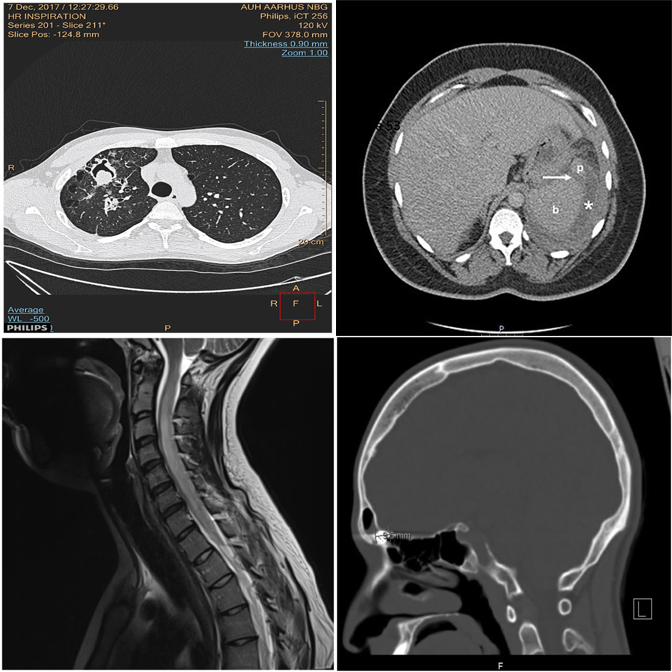

Basic modality mismatches in 2×2 grids. E.g., one MRI scan among CT scans.

Correctly identifies the MRI scan as the modality outlier.

Exhibits strong position bias — always defaults to A regardless of content.

Picks the wrong quadrant despite the correct region.